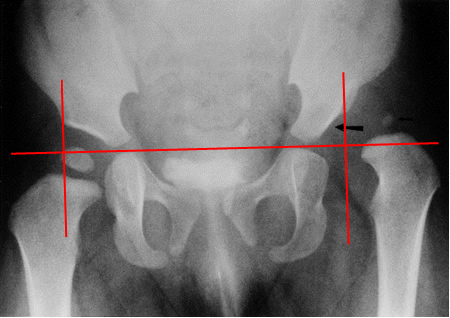

La radiografia ha un ruolo nella diagnosi?

Certo! Pur non rappresentando il “gold standard” per la diagnosi precoce della DEA, può essere molto utile nel caso di lussazione vera della testa femorale, per confermare la risalita del femore al di fuori della sua sede naturale. Similmente la radiografia assume il suo valore quando lo perde l’ecografia, ovvero quando le dimensioni del nucleo di ossificazione della testa femorale “oscurano” il fondo aceta bolare impedendo la corretta valutazione dell’articolazione con gli ultrasuoni, sia nella diagnosi della DEA in un bambino già grande, che nei controlli dei bambini in terapia. (Fig. 13)

Fig. 13